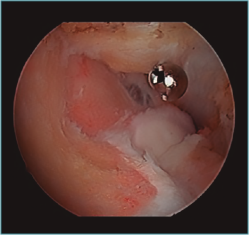

Cirugía artroscópica

La artroplastia osteocapsular artroscópica persigue los mismos objetivos que la cirugía abierta, con una serie de ventajas como son la menor incisión, la menor agresión para las partes blandas, la disminución del sangrado intraoperatorio y la mayor precisión en el fresado y recontorneado óseo, al contar con la magnificación proporcionada por la óptica, así como el mejor control del dolor del paciente en el postoperatorio y el comienzo precoz de la rehabilitación. Sin embargo, es un procedimiento demandante técnicamente que exige tener una amplia experiencia previa con procedimientos más simples. Los factores que aumentan la complejidad del procedimiento con respecto a otro tipo de artroscopias del codo son, dejando aparte los relacionados con la causa que desencadenó la rigidez, que ya fueron mencionados: el volumen articular reducido, la escasa distensibilidad de la cápsula engrosada y la presencia de cicatrices intraarticulares e hipertrofia sinovial, que dificultan de manera importante la visualización y el trabajo articular que tenemos que hacer. Esto, sumado a la restricción de 2 horas de isquemia como máximo de las que disponemos, puede poner en jaque a cirujanos inexpertos que tengan que terminar el procedimiento sin haber conseguido concluir los objetivos del tratamiento (Figura 7).

Figura 7. Sinovitis exuberante que no deja ver la articulación radiocapitelar desde el portal anteromedial proximal, en una artritis postraumática con volumen articular reducido.